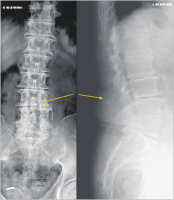

LWS

Abbildung 1: Röntgenaufnahmen der LWS in zwei Ebenen mit Nachweis des röntgendichten Markierungsfadens der links neben dem Dornfortsatz von LWK 3 zurückbelassenen Kompresse.